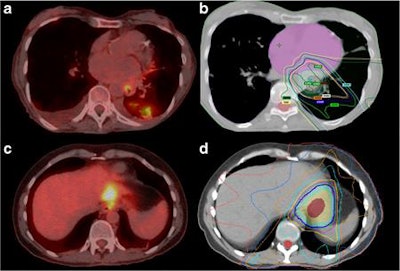

Thus the objective of this study was to assess FDG-PET/CT's ability to detect and to diagnose interval metastasis and identify predictors of interval metastases in a large cohort of patients with esophageal cancer.

The subjects underwent an FDG-PET/CT scan (Discovery RX, ST, or STE; GE Healthcare) before and after completion of chemoradiotherapy. After fasting for six hours, patients received between 555 and 740 MBq of FDG.

In reviewing the FDG-PET/CT results, Goense and colleagues observed 109 patients (14%) presented with new potential metastatic lesions during restaging. Of these patients, 65 cases were true-positive results (8.3%) confirmed through clinical follow-up (44 patients, 68%) or by histology (21 patients, 32%). By comparison, there were 44 false-positive (5.3%) results.